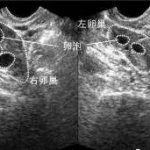

输卵管堵塞有哪些症状?

3、导致不孕:输卵管是精卵结合的通道,当输卵管发生堵塞的时候,精子无法和卵子结合,所以直接就导致不孕。多年不孕的女性,一定要检查输卵管是否通畅。

4、诱发宫外孕:宫外孕的发生可能与输卵管通而不畅有关,导致受精卵不能更加顺利的经过输卵管进入宫腔,而是停留到输卵管部位着床,宫外孕是非常凶险的妊娠方式,一定要引起重视。

输卵管堵塞以及月经不调都是导致女性不孕的病症,输卵管堵塞主要导致女性不孕,占女性不孕的25%至35%,输卵管堵塞与女性正常的月经来潮可以说是没有直接关系的,月经的来潮是受体内激素的调节和控制,这些环节与输卵管都是不沾边的,所以输卵管堵塞不影响月经的正常来潮。